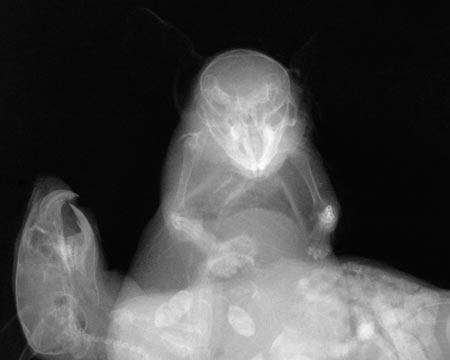

Wim DELVOYE | |||